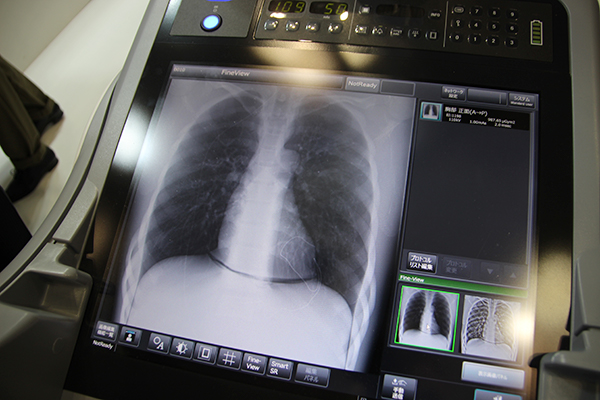

全世界3500台以上の実績を持つ回診用X線撮影装置MobileDaRtに,第8世代のMobileDaRt Evolution MX8 Versionが登場した。卵のような“丸い”印象を与えるデザインで,第7世代の「MX7」から雰囲気が一新。展示のキーワードでもある働き方改革を意識し,撮影業務を行う診療放射線技師が少しでも楽に扱えることをコンセプトに開発された装置である。まず,病棟内を安全に移動しやすくするため,X線管球の支柱を伸縮構造とし,走行時には1.27mの高さにすることで前方視野を確保した。本体幅も56cmに狭小化することで,装置の前方車輪のあたりも視認しやすくなっている。回診業務で,ベッドの間やエレベーターなど狭い場所に入る際の取り回しに威力を発揮するモーターアシスト駆動もMX7より向上させた。これにより,本体の操作もさらにスムーズに行える。走行時には,操作者の身長に合わせてハンドルの高さを調整できるオプションも準備し,楽な姿勢で安全な走行をサポートする。また,X線管球ハンドルの上下2か所にロックボタンを設けたほか,コリメータ操作ダイヤルも管球の前面・後面につけたことで,撮影時の操作性も向上している。

本体には,19インチモニタを搭載。MX7の17インチから拡大したことで撮影後の画像確認をしやすくなり,フルフラットのため清掃も容易だ。このほか,収納ポケットに入れたFPDの盗難紛失を防ぐロック機能や,小物の収納スペースなど,効率的に回診業務を行うための細やかな工夫が施されている。

MX8 Versionは,ユーザーのニーズに合わせてDRを組み合わせられるDR“NEUTRAL”2.0対応のシステムで,日本国内では,2018年1月にキヤノン社製,富士フイルム社製のDRに対応するタイプを先行して発売。そして,4月に島津社製DR搭載のiタイプが発売となった。iタイプには,グリッドレス撮影が可能な画像処理機能“Smart SR”に加え,新しい画像強調処理オプション“Fine-View”が搭載可能となっている。Fine-Viewはチューブやガーゼといった体内の異物を強調表示する画像処理で,ワンボタンで通常の撮影画像と切り替えて表示でき,カテーテルの位置確認や術後の遺残確認を簡単に実施できる。設定により通常画像とともにFine-View画像をPACSに転送することも可能だ。また,回診業務を支援する機能として,支柱を格納してもモニタ隅に次の検査の行き先を表示する機能もiタイプに搭載された。次の検査の病室番号や撮影部位,医師からの指示などを走行しながら確認できることで,スムーズに次の撮影操作に入ることができる。

遺残確認が容易な“Fine-View”

支柱を格納しても行き先が表示される機能を搭載